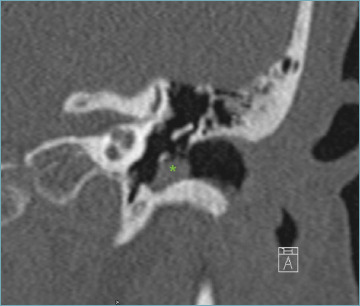

Abstract Image